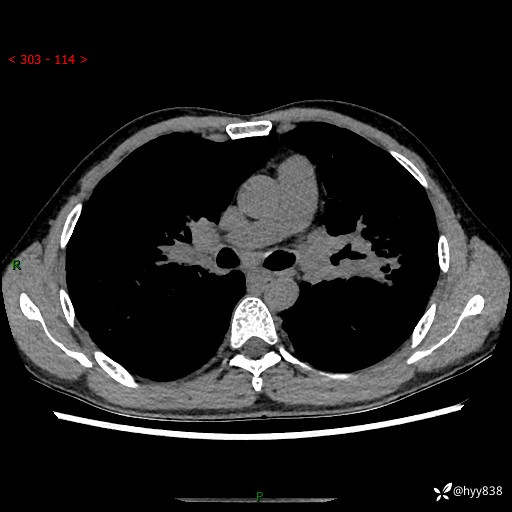

中年男性,咳嗽咳痰1月余。细看:肺、肺门、气管,貌似都有问题---(有结果)

现病史:患者于1个月前受凉后出现间断性咳嗽,伴白色泡沫样痰,无发热寒战、咯血、胸痛胸闷、恶心呕吐、呼吸困难等特殊不适,起初未予特殊处理,后患者就诊当地中医医院,查胸部CT提示支气管炎并双肺感染性病变,经抗感染(哌拉西林舒巴坦),止咳化痰(溴己新、三拗片)等治疗后,患者自诉咳嗽咳痰症状较前缓解,未诉发热等其他特殊不适,近期复查CT提示“肺部感染灶未见消退,双侧肺门增大,双肺散在小结节”,今为求进一步诊治,前来我院就诊,门诊以“肺部感染”收住入院。 患者自起病来精神、食欲、睡眠尚可,大小便正常,体力、体重无明显变化。

胸部CT平扫+增强(两期)